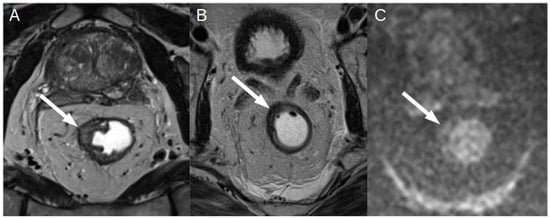

3.1. T Staging

3.2. N Staging

3.3. New Techniques and Applications